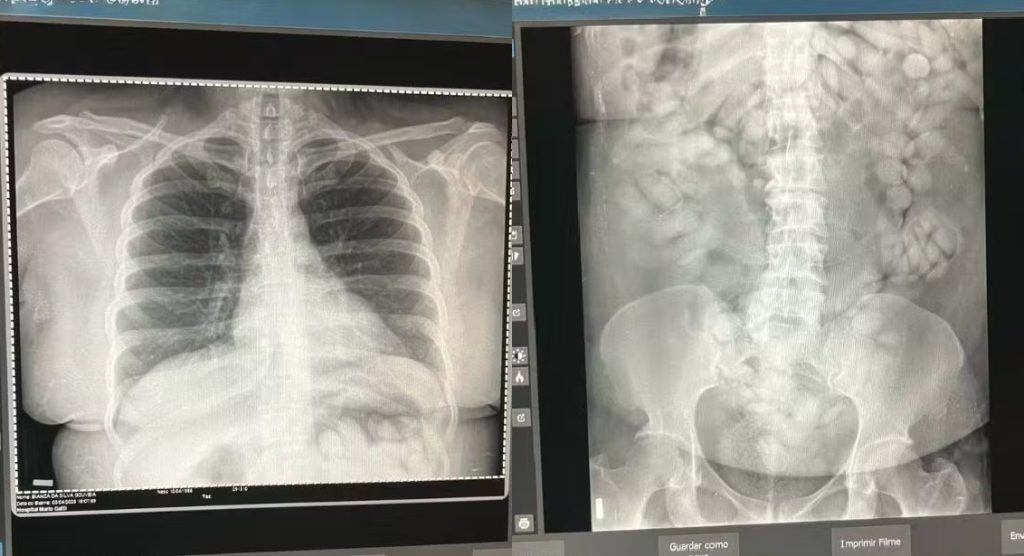

Uma mulher foi presa pela Polícia Federal na última quinta-feira (3) ao tentar embarcar para a França levando 100 cápsulas de cocaína no estômago. A prisão ocorreu no Aeroporto Internacional de Viracopos, em Campinas (SP), durante uma fiscalização no Terminal de Passageiros.